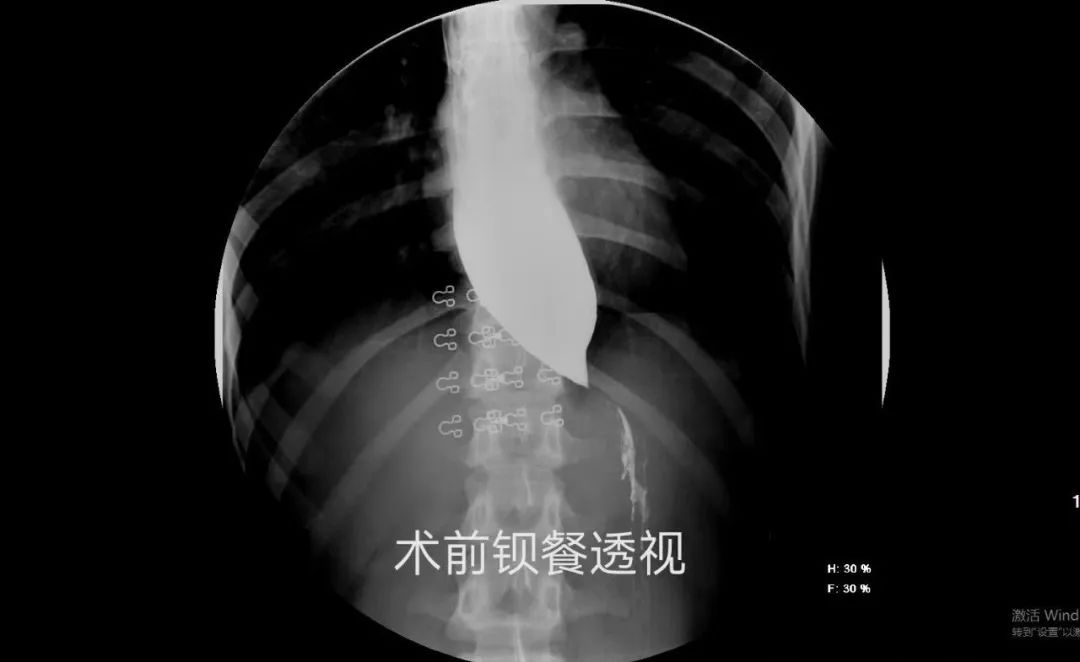

张先生,20岁,4年前开始出现进食梗阻感。为解决进食困难,他曾多次在多家医院就诊。最后,他慕名来到我院普外临床医学中心。经过详细的术前检查评估,患者顺利接受了经口内镜下食管括约肌切开术(POEM 术)。术后第三天,患者在喝水时就感觉胸口一下子“松快”了。之后经评估可进食,吞咽困难的症状完全改善。